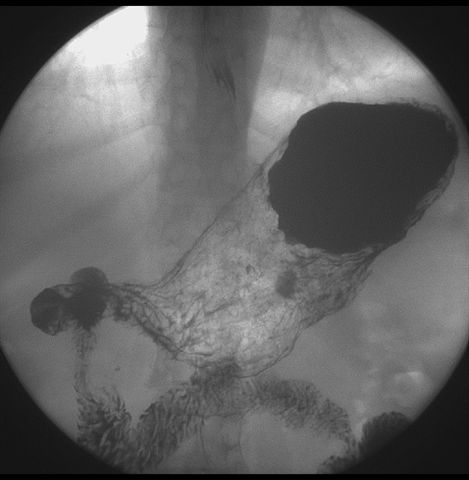

标题: X6872:F,69y,胃部不适。

胃窦至幽门段胃壁僵硬,扩张受限,局部纠集粘破坏,呈杵状。提示溃疡癌变可能性大。

胃窦癌可能性大,建议胃镜活检。钡剂太稀,吃的有点多。

支持考虑胃窦癌可能,胃内滞留液太多,胃窦部僵硬。

瀑布型胃,胃粘膜那是一个乱,窦部充盈不好,第16幅窦部粘膜反倒又很顺,先定个胃炎胃窦炎胃窦癌待排之类,建议进一步作胃镜检查。

胃窦部见钡池影,局部粘膜紊乱,纠集呈杵状改变,胃壁扩张受限,胃窦癌可能性大,建议胃镜检查.

胃窦部管腔扩张度较差,形态略有改变,胃窦粘膜显示欠佳,胃窦部占位可能性大,结合胃镜活检。

胃窦部狭窄、稍僵硬,考虑胃窦癌?建议胃镜检查。

北京肿瘤医院胃镜诊断皮革胃。